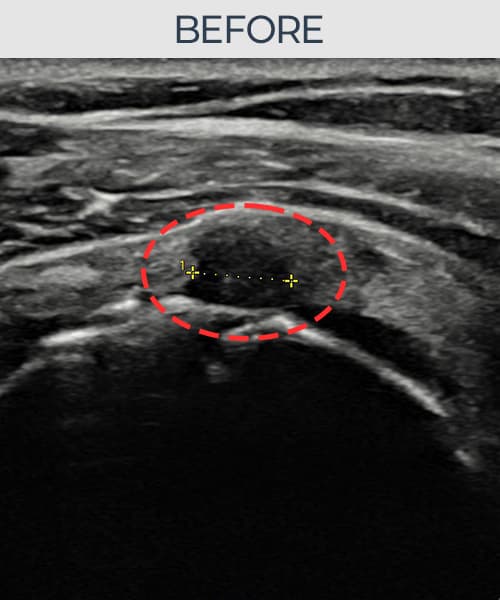

[経過期間: 23.07.18~23.09.14]

[縫縮術] 超音波検査にて左 棘上筋腱 광범위 部分断裂(15mm × 6mm (腱厚の約70%欠損))を確認。縫縮術施行後、腱の連続性が回復し、日常生活に復帰されました。